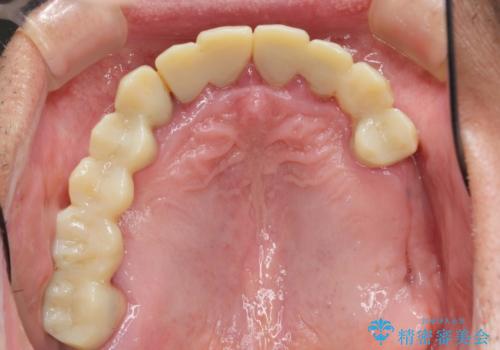

- 他院で上顎は全て抜歯し、入れ歯にする必要があると言われ相談に来院されました。

検査の結果、重度の歯周病であることから保存が難しい歯は抜歯を行いインプラントを、残すことが可能な歯には再生治療を含めた歯周病治療を行いより多くの歯を残す歯周病治療を計画します。

上顎は、残っている前歯も揺れがあり残すためにはクラウンでつなぐ歯周補綴が必要な状態です。

また咬合負担に不安のある前歯を助けるためにも、臼歯部にインプラント補綴を行いしっかりとかめる状態とすることも大切です。